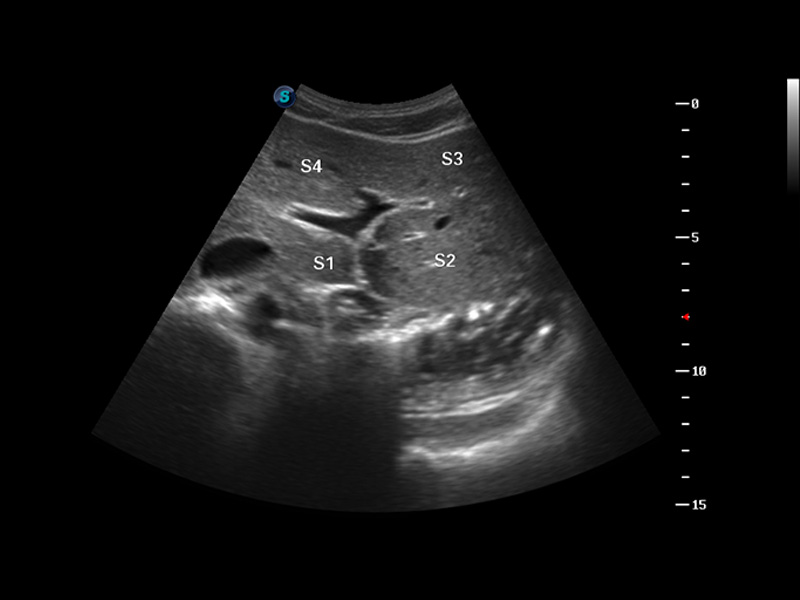

3D/4D成像